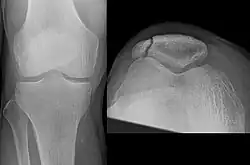

The patella can break in various ways depending on the way it is injured, and into two or more pieces.[1] Types include transverse, with one fracture line and is the most common type,[5] marginal, osteochondral and the rare vertical type, or stellate, where a direct compression force gives rise to a comminuted pattern.[5][7] Patella fractures can be further classified as displaced, where the broken ends of bone do not line up correctly and separate by more than 2mm, or undisplaced and stable where pieces of bone remain in contact with each other.[1][7] If fragments of patella bone stick out from the skin it is known as an open patella fracture, and closed if the overlying skin is intact.[1]

Comminuted fracture of patella -

Osteochondral fracture of patella -